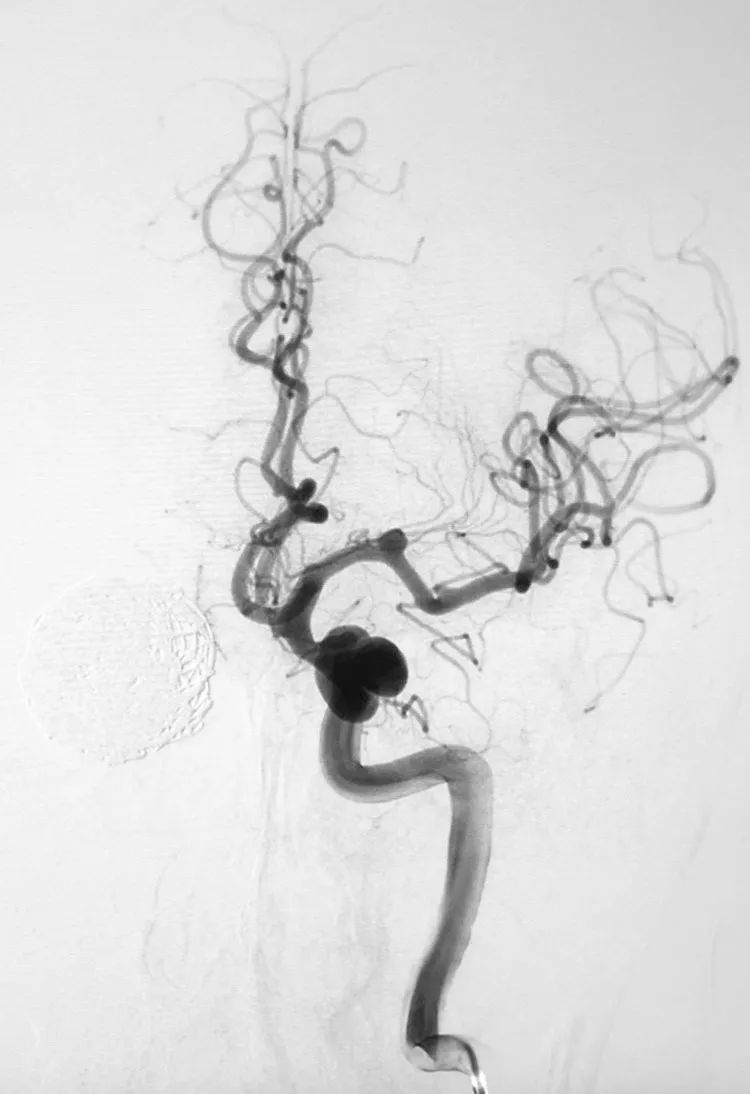

完全释放Tubridge®密网支架。

术后右颈内动脉正侧位造影显示:右大脑前动脉不显影,考虑为血流动力学因素所致。

转行左颈内动脉正位造影证实前交通动脉开放。

左侧颈内动脉床突段及左侧大脑中动脉M1段也有多发动脉瘤,等待三期治疗。